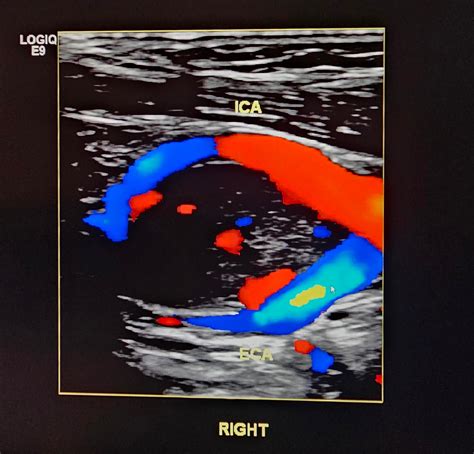

Ultrasound (Doppler) To visualize the mass and evaluate the vascularity and blood flow patterns.

• carotid body tumor ultrasound images